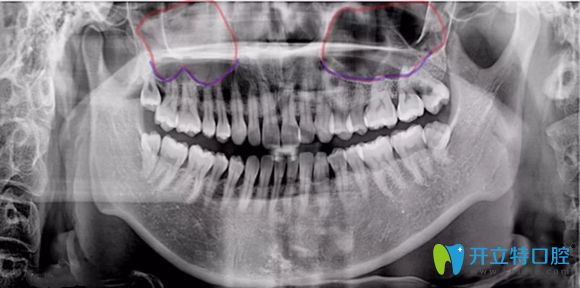

部分做種植牙的朋友,可能會聽到醫(yī)生說,你需要再做個上頜竇提升,這樣才能保證種植效果。那么,問題來了,什么是上頜竇提升呢?做種植牙時上頜竇提升危險嗎?有什么風(fēng)險沒?對此呢,小編覺得還是有必要給大家科普下:上頜竇內(nèi)提升術(shù)和上頜竇外提升術(shù)究竟是什么,弄清之后,大家也就知道它是否有危險了。

簡單來說,上頜竇提升術(shù)是由于患者上頜骨高度不足,使種植體不能有效埋入,固位不行,就需要增加上頜骨高度而產(chǎn)生的手術(shù)。主要分兩種方式及內(nèi)提升和外提升。

內(nèi)提升它是指不用做額外切口,就在種植體窩洞處,用敲擊法,或者是超聲骨刀磨除上頜竇底的骨質(zhì),使上頜竇底提升。同時植入骨粉,使牙槽骨的高度也增加,這樣就能使種植體可植入的長度增加,內(nèi)提升創(chuàng)傷較小,是臨床常用的方法。

外提升它適用于上頜骨高度極度不足,一般少于4mm,該情況下,可從上頜竇外側(cè)壁的骨板開窗打開上頜竇,剝離上頜竇底粘膜,植入骨粉來達(dá)到增加種植區(qū)域骨高度的術(shù)式。